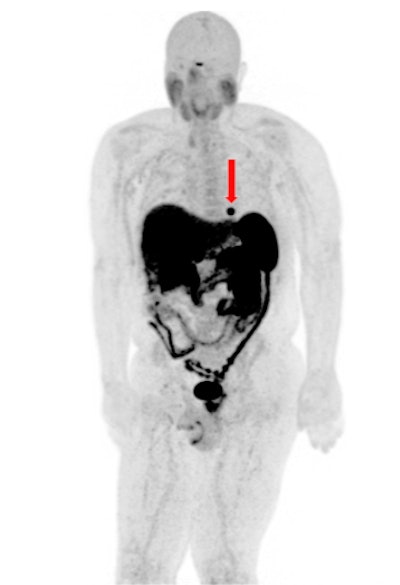

PET/CT has no rivals when it comes to the detection and surveillance of cardiac metastases in well-differentiated gastroenteropancreatic neuroendocrine tumors (GEP-NETs) as well as guiding clinical management, according to research presented at the annual congress of the European Association of Nuclear Medicine (EANM 2020).

"Chest CT demonstrates poor sensitivity for detection of cardiac metastasis, with cardiac MRI performing much better. Still, neither CT nor MRI is as sensitive as [gallium-68 (Ga-68)] DOTATATE PET/CT for detection of neuroendocrine cardiac metastasis," noted Dr. John Renfrew and colleagues from the Mayo Clinic in Phoenix, Arizona, U.S.

Evidence from the Mayo Clinic confirms that the prevalence of cardiac metastasis is associated with high tumor burden, and an average of 2.7 other organ systems are also involved when these metastases are seen. Further, patients typically demonstrate a Krenning score of 3-4 when they have cardiac metastases.

The group evaluated the prevalence, distribution pattern, and radiotracer uptake characteristics of cardiac metastasis on Ga-68 DOTATATE PET/CT. On PET images, they documented and analyzed the maximum standardized uptake value of the cardiac metastasis and left ventricular chamber (blood pool), the Krenning score of the cardiac metastasis, and the presence of multisystem metastasis. They performed correlation with diagnostic CT and/or cardiac MRI to confirm the location of metastasis in the heart.

Between October 2017 and March 2020, 1,426 Ga-68 DOTATATE PET/CT and PET/MRI scans were performed at the Mayo Clinic in Arizona. Twenty-six patients (mean age, 64 ± 10.17 years; male to female ratio of 11-to-10) were diagnosed with a cardiac metastasis, always with coexistence of multisystem metastases.